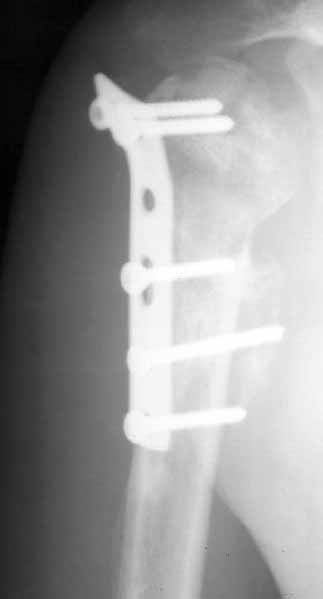

A male 25 y.o. after a car accident Aug 16, 2002 sustained a fracture of the proximal humerus (image 1), Sep 5 ORIF performed elsewhere.

Image 1